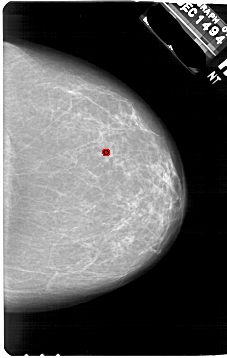

A_1751_1.RIGHT_CC

RIGHT_CC LINES 6796 PIXELS_PER_LINE 4306 BITS_PER_PIXEL 12 RESOLUTION 43.5 OVERLAY

FILE: A_1751_1.RIGHT_CC.OVERLAY

TOTAL_ABNORMALITIES 1

ABNORMALITY 1

LESION_TYPE CALCIFICATION TYPE PLEOMORPHIC DISTRIBUTION CLUSTERED

ASSESSMENT 4

SUBTLETY 2

PATHOLOGY BENIGN

TOTAL_OUTLINES 1

BOUNDARY